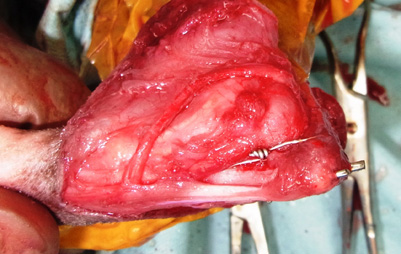

前十字靱帯断裂

手術写真①

膝関節の前十字靱帯の断裂部位

手術写真②

靱帯断裂により、膝関節が不安定になり、

変形性関節症を起こしている様子

手術写真③

断裂した靱帯の変わりに自己の大腿筋膜と

支持帯を用いて靱帯の再建を行う。

手術写真④

筋肉、皮膚を縫合し、終了